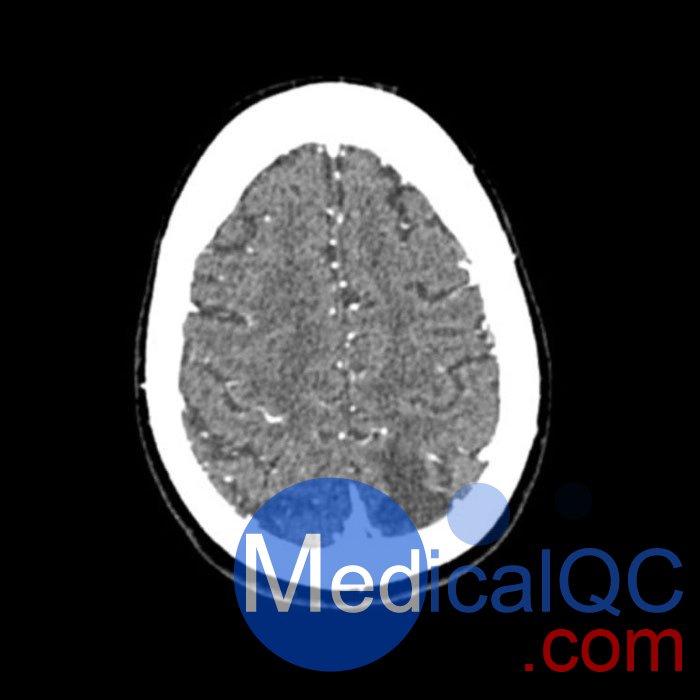

WEK50-03動脈瘤頭模,WEK50-03血管造影CTA頭模是頭部 CTA 動脈瘤模型

模擬造影劑動脈期頭部增強(qiáng)(CT血管造影)。 它覆蓋了頂點(diǎn)枕骨大孔。

模型有三個顱內(nèi)動脈瘤

大腦中動脈 (MCA) 的前部

交通動脈 (ACoA) 和基底動脈動脈。

該體??捎糜贑T(包括CBCT)評估和優(yōu)化成像性能和人工智能診斷。 這是也適合培訓(xùn)目的。

WEK50-03動脈瘤頭模,WEK50-03血管造影CTA頭模影像圖:

更多效果和DICOM數(shù)據(jù)請聯(lián)系我們